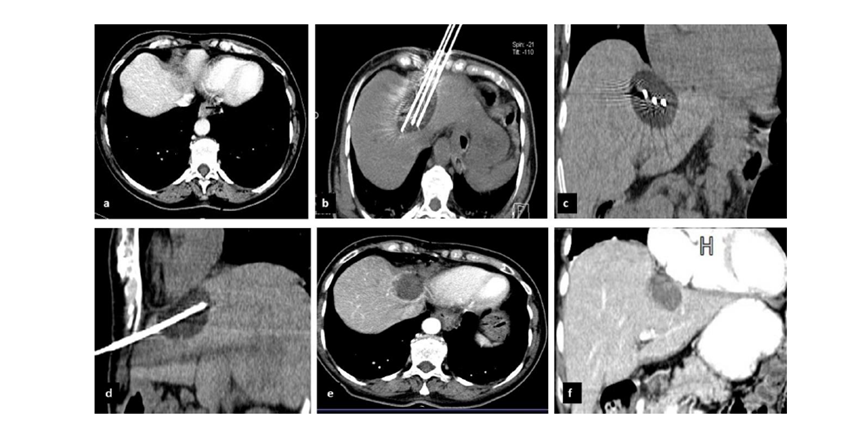

CT引導的冷凍消融

(c) 19個月后隨訪,沒有發(fā)生局部腫瘤進展。完全消融率為97%(66/68);2名患者均接受了額外的冷凍消融,隨后實現(xiàn)完全消融。平均隨訪期為 12.8 個月(范圍:3-27 個月)。所有患者均接受影像復查(CT 或 MRI)。11個病灶(16.2%)檢測到局部腫瘤進展,6、12和18個月時的累積局部腫瘤進展率分別為4%、8.2%和20.5%。8例出現(xiàn)遠處肝內(nèi)或肝外病變的患者接受經(jīng)動脈化療栓塞、經(jīng)動脈化療栓塞加射頻消融治療或全身化療。

(a)軸向CT顯示病變位置毗鄰心臟和上腔靜脈(黑色箭頭)。1個月后的軸向(e)和冠狀位(f)增強CT掃描顯示低密度區(qū)域,由于肉芽組織反應引起的邊緣增強。